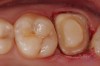

Case 1

A Class IN maxillary bicuspid was previously restored with a fiber post and an all-porcelain crown (Figure 1). The forces of the oral environment resulted in fracture of the fiber post and crown failure. The remaining fiber post in the root was removed, and anti-rotational areas were prepared for a cast post (Figure 2). A gold cast post was constructed at a dental laboratory, using an indirect technique (Figure 3). A porcelain-fused-to-metal (PFM) crown was constructed with a bevel finish to provide a ferrule and reduce forces on the post (Figure 4 and Figure 5).

Figure 1  X-ray of an endodontically treated second bicuspid restored with a fiber post, core, and all-porcelain crown.

Figure 1